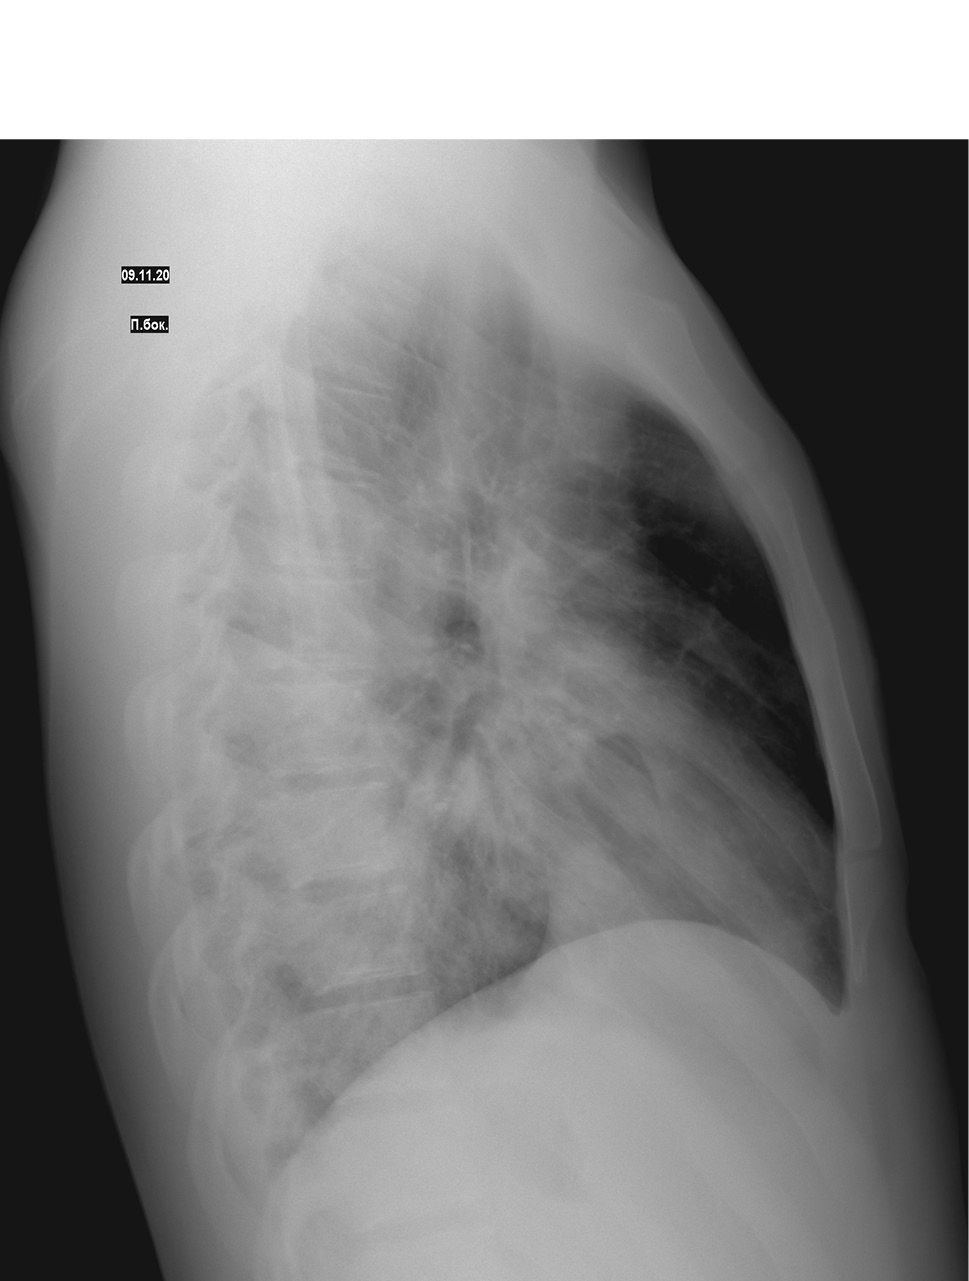

На фоне проводимой терапии у пациента в клинике сохранялись диарейный синдром, интоксикация, гипертермия. Состояние ребенка ухудшилось за счет появления признаков дыхательной недостаточности (затруднения дыхания, одышки, падения сатурации). В динамике выполнена контрольная рентгенография органов грудной клетки 09.11.2020: по сравнению с предыдущей обзорной рентгенограммой № 5189 от 06.11.2020 — отрицательная динамика в виде появления новых очагов слева и справа; двусторонняя очагово-сливная пневмония: справа — S4, S5 средней доли и S8, S9 нижней доли, слева — S4, S5 верхней доли S8, S9, S10 нижней доли (рис. 1, 2, 3).

Рисунок 1. Рентгенологическое исследование легких в прямой проекции

Рисунок 2. Рентгенологическое исследование легких в правой боковой проекции

Рисунок 3. Рентгенологическое исследование легких в левой боковой проекции

На рентгенограмме органов грудной клетки в динамике от 16.11.2020 отмечена положительная динамика с признаками уменьшения инфильтрации легочной ткани.